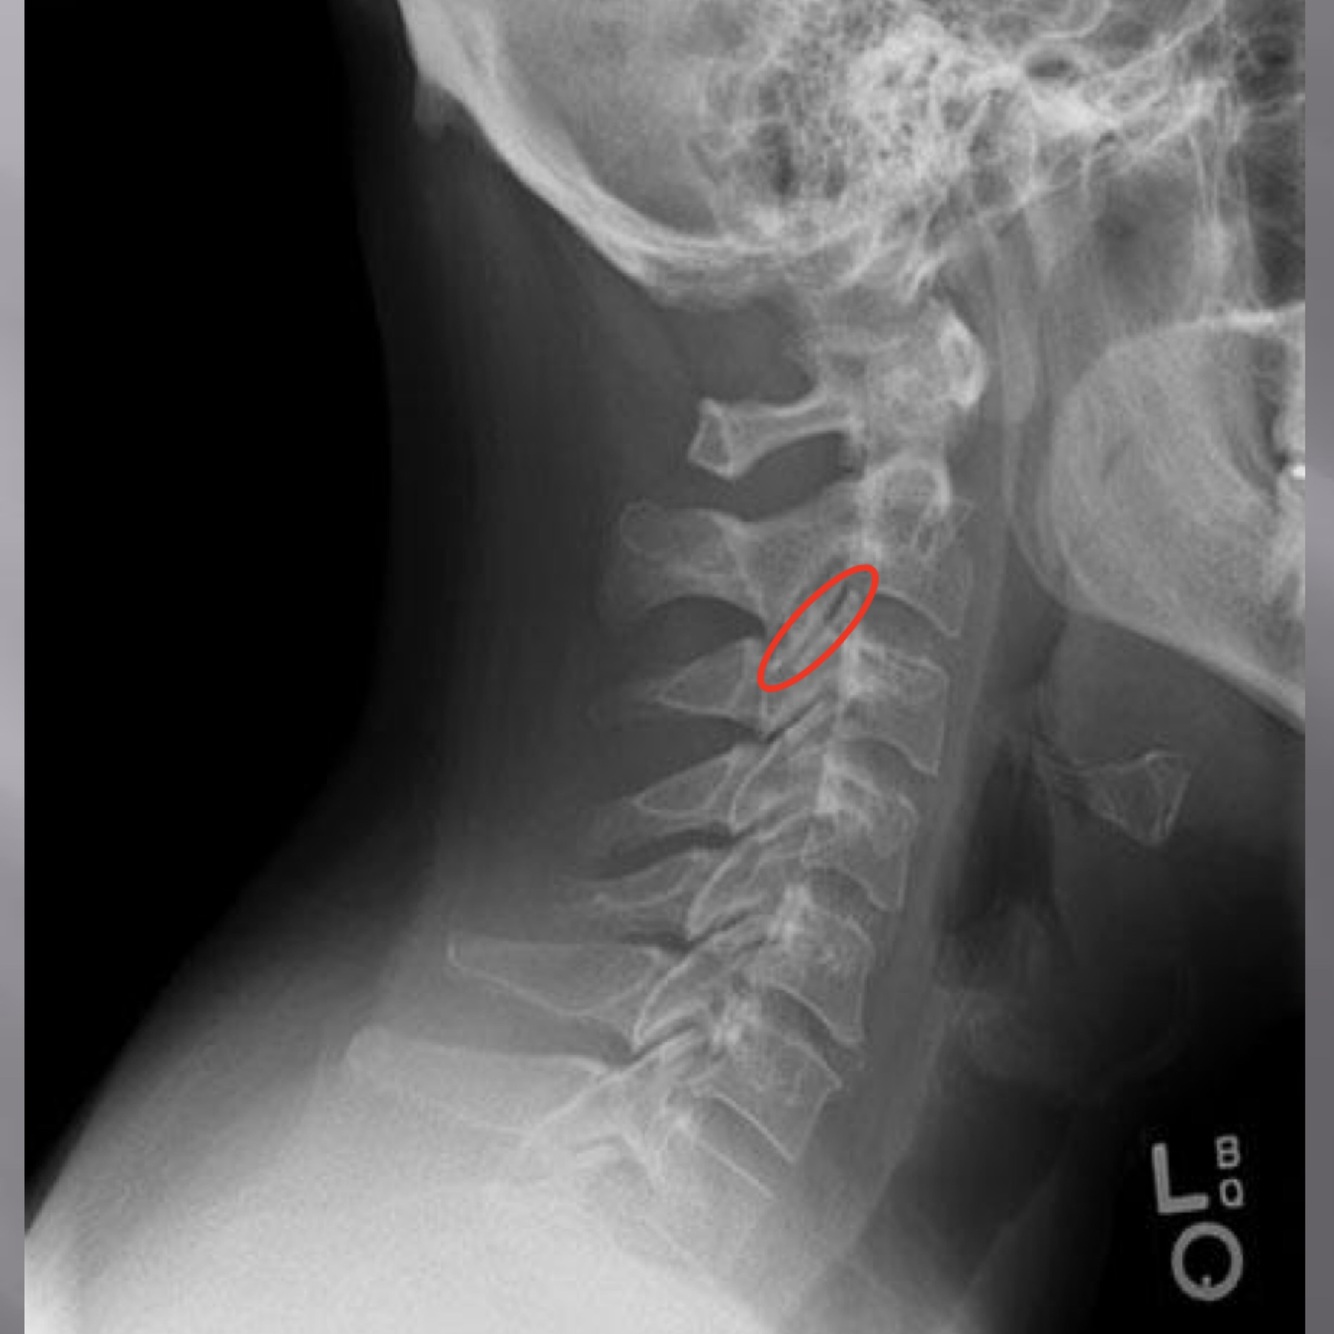

LATERAL CERVICAL LANDMARKS lateral cervical view

external acoustic meatus

mastoid process (air cells)

posterior tubercle of c1

angle of mandible

EOP

spinous process C2-C7

sella turcica

dens

posterior arch of C1

lamina c2-c7

uncovertebral joints (joints of luschka)

vertebral body c2-c7

lateral masses c1

rami of mandible

articular processes

body of mandible

transverse process of c2-c7

anterior tubercle c1

zygapophyseal joints

frontal sinus

petrous portion

occipital condyle

superior endplate tips

inferior endplate tips

Lateral cervical view

disc spaces

26

atlanto-dental interspace

27

hyoid bone